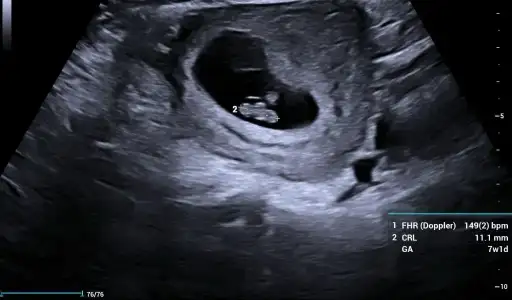

Kızlar benimkinide tahmin edin yaa kese yuvarlakmı ovalmi ben anlamıyorum burda 6+4 😂😂